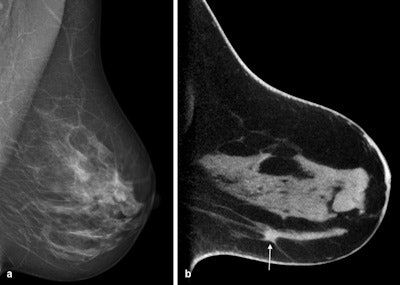

Cone-beam breast CT, contrast-enhanced examination. Each image shows the coronal single slice with invasive ductal breast carcinoma on the right. A: Prior to administering the contrast agent, only dense glandular tissue (ACR IV) and a calcified particle (arrow) in the tumor area. B: After administering the contrast agent, depiction of carcinoma portions with intense contrast agent uptake.However, even this method is somewhat dependent on the density of the breast: The detection rates are lower with dense breast tissue. In this case, the detection rate can be improved by administering a contrast agent. To evaluate how cone-beam CT fares against mammography, the researchers are now embarking on a larger clinical study, during which the team from Göttingen will collaborate with their peers in Norway and Berlin.